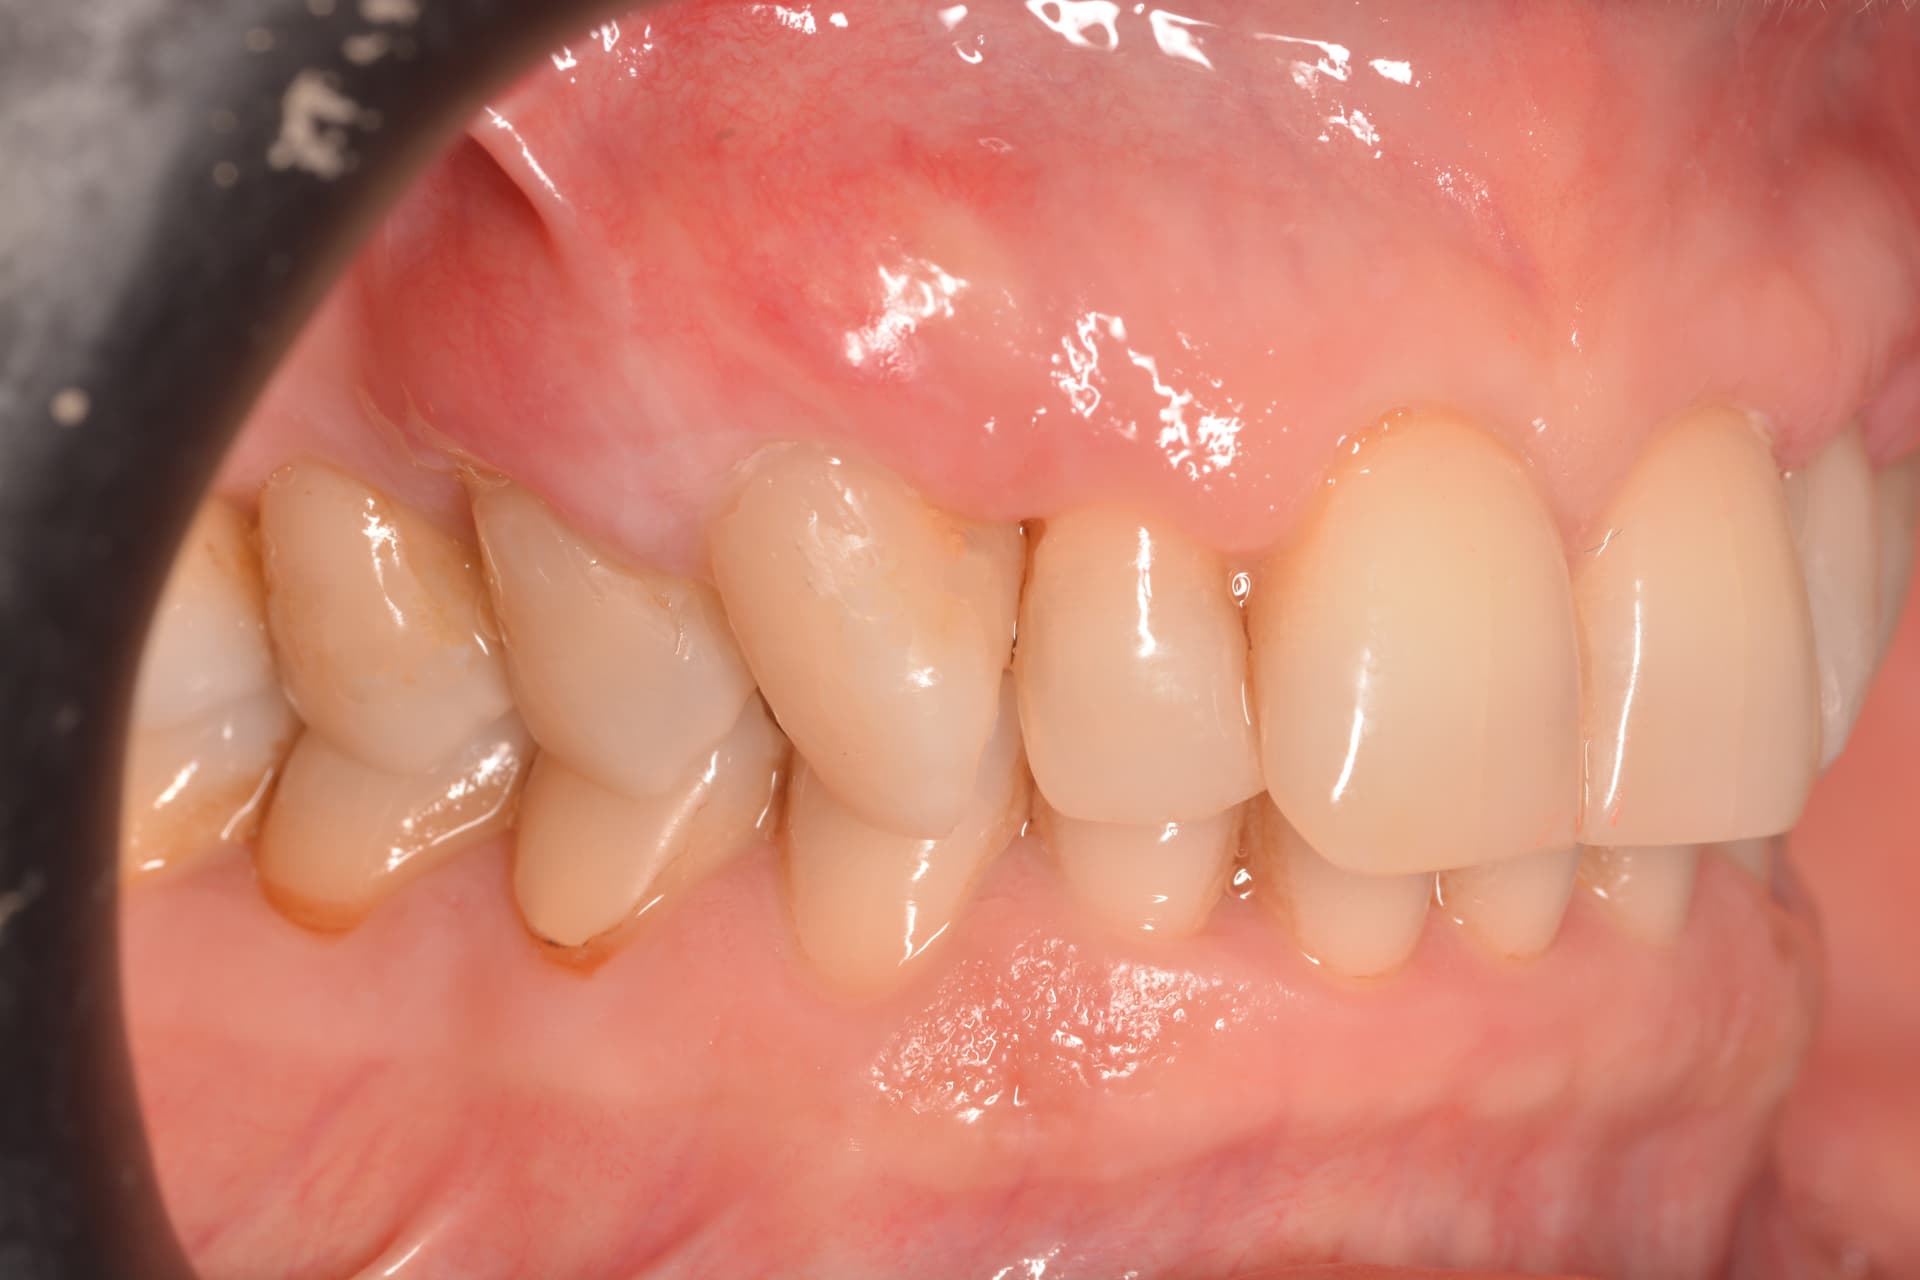

Injerto de tejido conectivo con técnica de túnel para cubrir recesiones radiculares